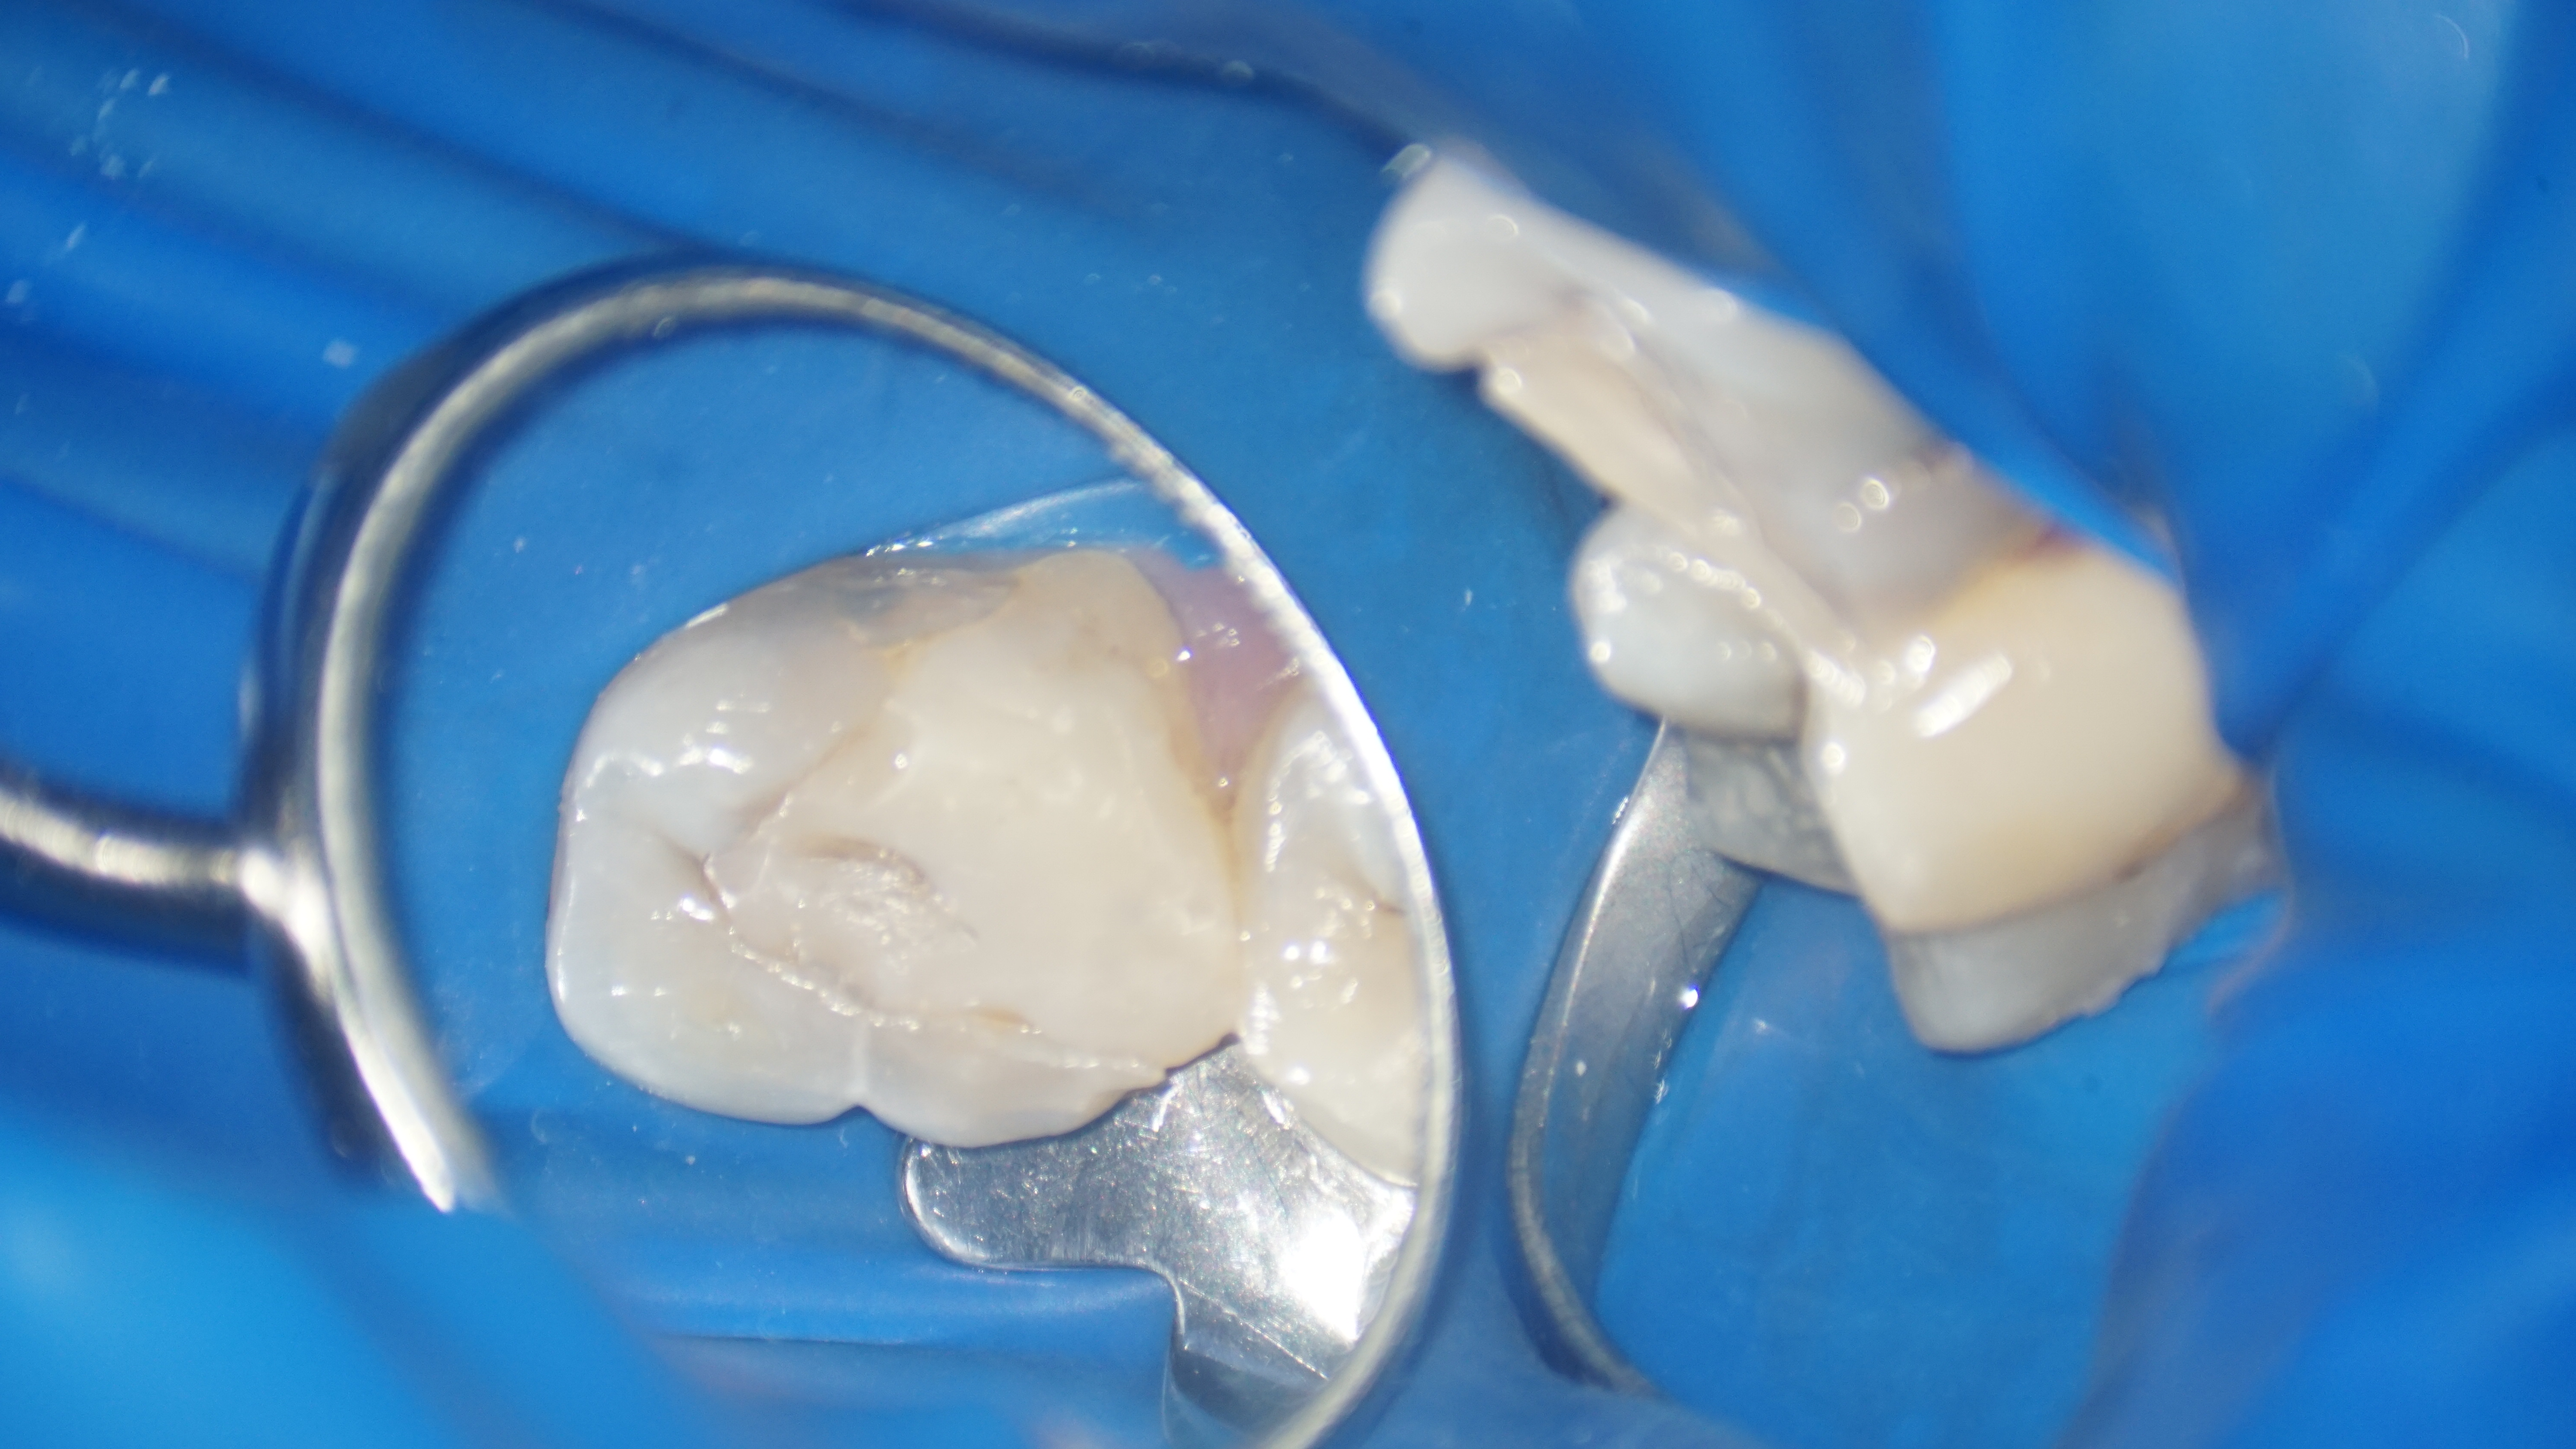

Astfel, s-a decis refacerea tratamentului iniţial, fapt ce a implicat instrumentarea canalelor radiculare și curățarea lor adecvată, realizând bypass-ul (ocolirea) fragmentului din rădăcina mezială şi înlăturarea celui din rădăcina distală. După finalizarea procedurilor, pacientul a raportat dispariția simptomatologiei și ameliorarea disconfortului la masticatie.

În concluzie, cazul a fost abordat cu succes prin efectuarea unui tratament endodontic și prin managementul al fragmentelor de ace ce împiedicau instrumentarea adecvată a spaţiului endodontic. Aceste proceduri au avut ca rezultat vindecarea patologiei și ameliorarea simptomatologiei, restabilind sănătatea și funcționalitatea dintelui.